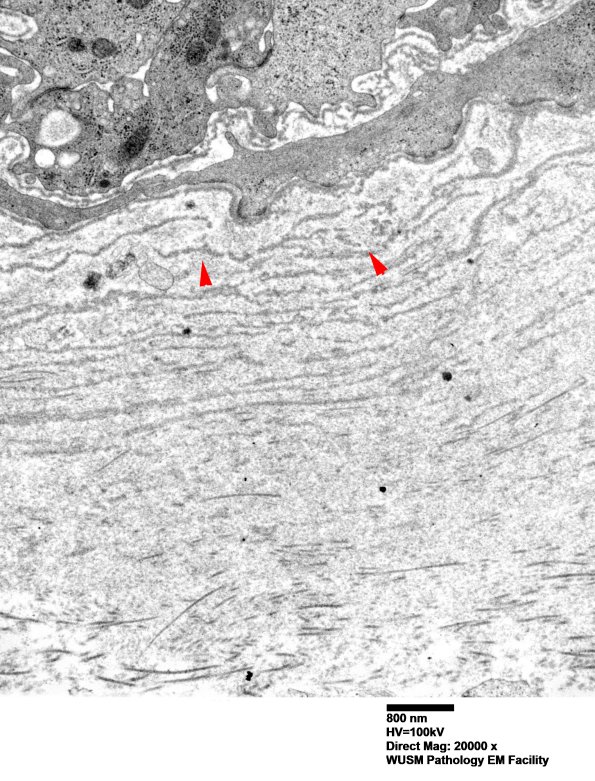

Washington University Experience | VASCULAR | Hypoxia-Ischemia, fetal-neonatal | White Matter | 6C3 (Case 6) EM 004 - Copy copy

6C3 (Case 6) EM 004 - Copy copy